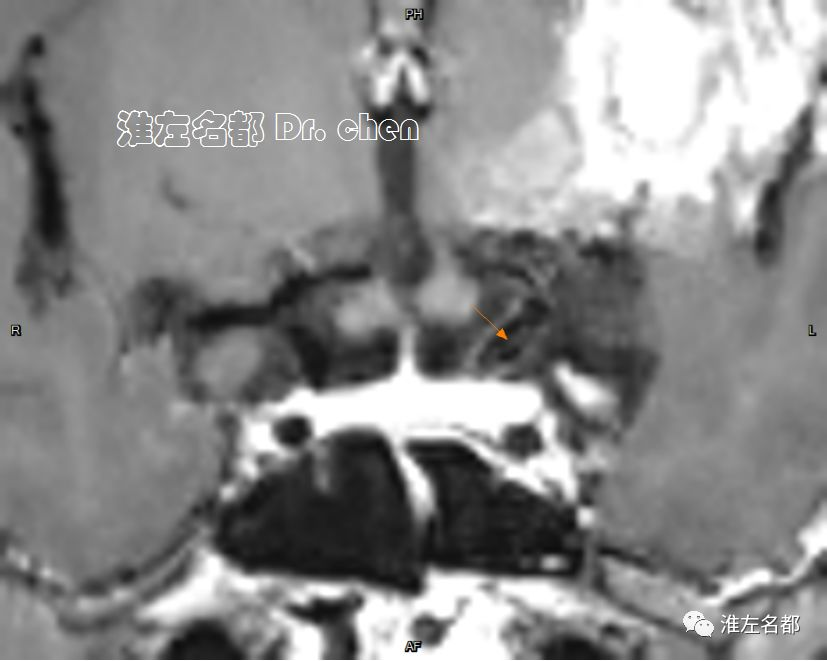

△管壁高分辨MRI(增强T1-SPACE):左侧颈内动脉末端检测到夹层“内膜征”(橙箭)。

3.脑动脉夹层临床确诊依赖于影像学检测到典型夹层征象:内膜征/双腔征、长段不规则/丝线样狭窄、壁内血肿、夹层动脉瘤等。本患儿DSA显示左侧颈内动脉末端和大脑中动脉主干长段狭窄,且大脑中动脉主干狭窄呈“丝线样”,符合夹层影像学征象。

6.在夹层真腔得以基本恢复后,DSA于左侧颈内动脉末端、大脑前和中动脉近端均检测到典型“内膜征”,进一步确定了夹层诊断。